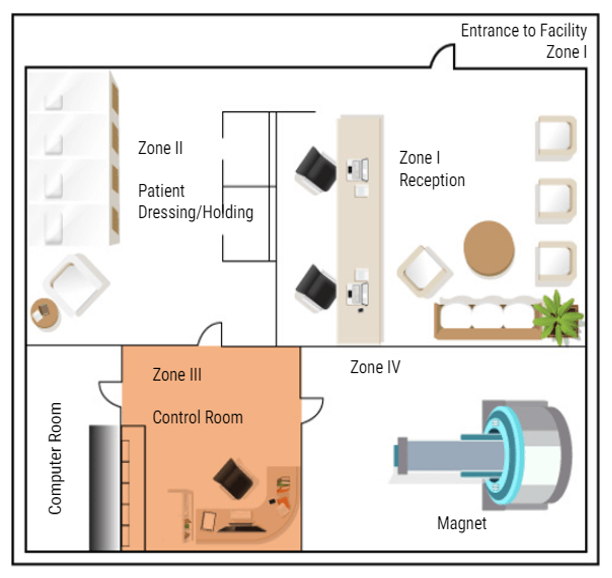

Now that we know what types of things to be concerned about in and around the MRI suite, we will now discuss MRI Zones and who can be in each zone.

Why Zones Are Important

In MRI we divide the work area into four zones. Each zone is very specific about who may enter and under what conditions. All zones must be marked in and around the MRI suite. There must also be a clear definition of where one zone ends and one begins, such as a doorway, chain/rope or another clearly visible sign. The signage should include who is allowed beyond that point. Let’s look at each zone:

Zone 1

Zone 1 is for the general public. Anyone can be in zone one. Some examples are hallways near the MRI area, the main waiting room, or a shared waiting area with other departments. There is NO screening needed to be in Zone One. While in zone one the patient may be asked to complete a screening sheet or be asked some basic safety questions before being moved to zone II.

Zone 2

Zone II is where a more thorough screening will take place. The patients will also be prepped for their scans in this area – changing clothes, removing all metal items and placing them in a safe place. Patients are only permitted to enter zone II when accompanied by a healthcare employee. Family members may also be permitted in Zone II accompanied by the healthcare worker without being screened. But this is the anyone not screened or cleared my go in the MRI area. ALL questions should be answered while the patient is in this area. Even if the patient has completed a screening form, they are not permitted beyond this point until they are cleared or accompanied by Trained MRI professionals.

Zone 3

The next zone is Zone three. This is the control area, where the MRI technologist would operate the scanner. Patients should be accompanied by an MRI safety trained individual to enter zone three. People who have not removed loose metals, or who have pacemakers or other unsafe medical devices, should not be permitted in zone III because of the proximity to zone IV. A screened but uncleared person may enter zone III ONLY under strict supervision by trained personnel, such as a patient who just wants to look at the MRI scanner to decide if they will be able to tolerate the exam.

Zone 4

The final zone is zone IV, the MRI scan room. ONLY CLEARED patients are permitted to enter Zone IV, accompanied by trained MRI personnel. The final step of clearance, while in zone III, should be to check the patient one last time for loose metals, other electronic devices and a last check of the critical screening questions. ACR suggests asking these questions a minimum of three times. Once At scheduling, once at screening and once at clearance. As an additional safety measure, many facilities build a metal detector into the doorway between Zone 3 and Zone 4. But there are hand-held devices that work well too and they are less expensive. Once the patient is cleared they can be taken into the MRI room and scanned.